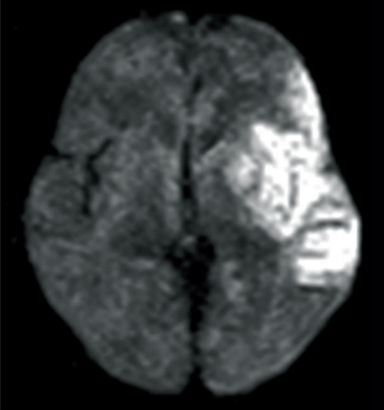

DWI